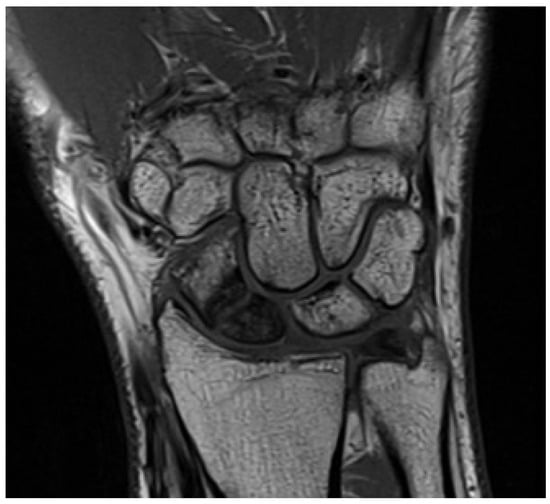

5.2. Magnetic Resonance Imaging (MRI)

Magnetic Resonance Imaging (MRI) is the most sensitive imaging modality for diagnosing TFCC tears and associated abnormalities. Its excellent soft tissue resolution allows for accurate visualization and characterization of TFCC tears, and it is invaluable for evaluating structures involved in DRUJ stability, such as the dorsal and volar radioulnar ligaments, especially after fractures (Figure 3). MRI also helps identify bone contusions and soft tissue injuries around the joint. However, MRI has limitations for patients with contraindications like metal implants or claustrophobia and may not be as effective as radiography or CT in assessing bone-related pathologies (Figure 4). Expertise in musculoskeletal imaging is crucial for proper interpretation of MRI findings [12,25,26].

Figure 3. Wrist MRI evaluation of the soft tissues (intact TFCC) following a scaphoid nonunion fracture.